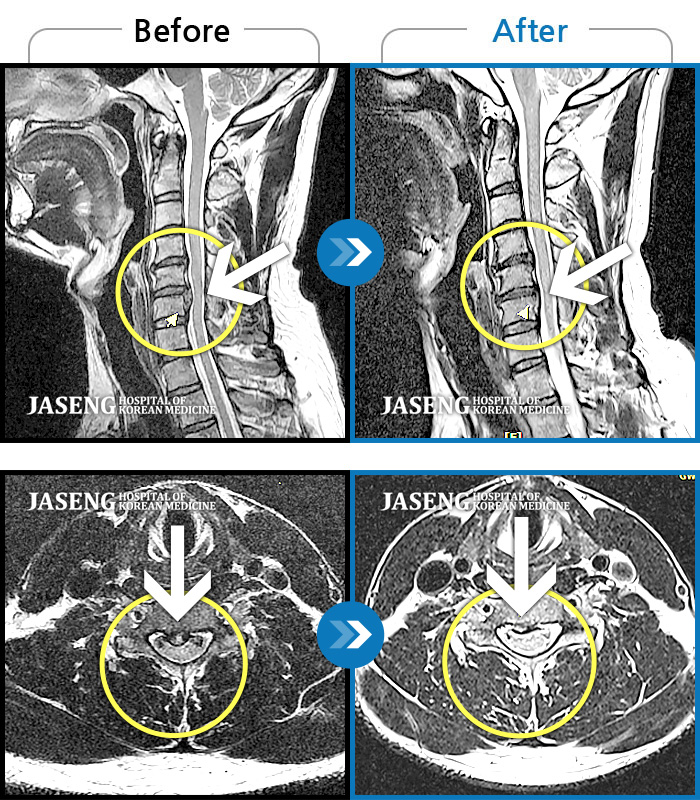

목디스크

광주 · 김동은 원장

후경부에서 견갑골까지 이어지는 묵직한 통증과 좌측 상지부위 저림

촬영시기

2018.03.12 ~ 2020.12.21

2020.12.24

조회수 69